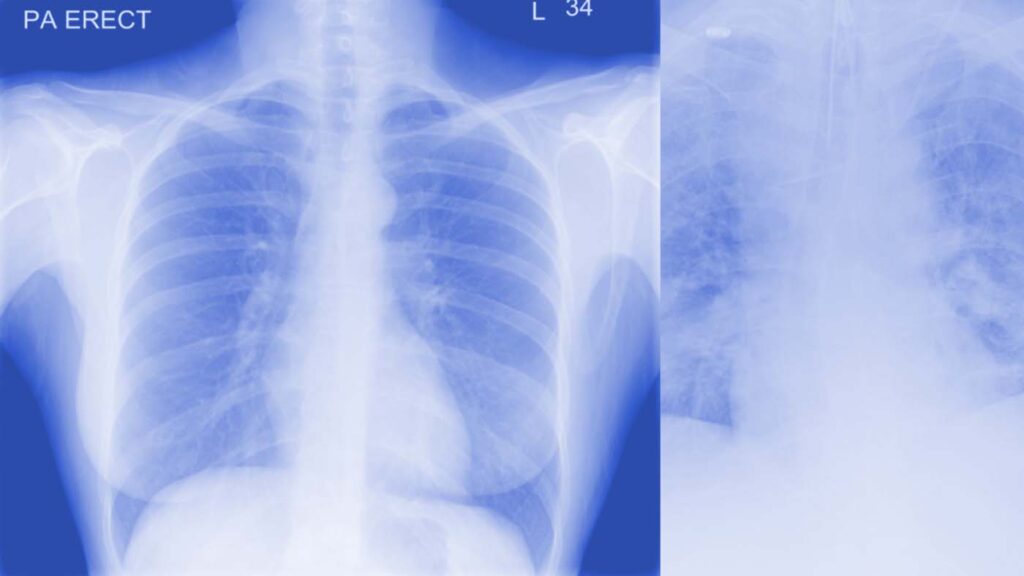

Supporting clinicians to assess COVID-19 severity using AI and Chest X-rays

COVID-19 X-rays have been a recommended procedure for patient triaging and resource management in intensive care units (ICUs) throughout the COVID-19 pandemic. Microsoft Research team worked closely with our clinicians at University Hospitals Birmingham NHS Foundation Trust to model radiological features with a human-interpretable class hierarchy that aligns with the radiological decision process. The model outperformed the clinicians across all hierarchical and multi-class tasks. To better understand the model’s failure patterns, the team employed an error analysis tool in Azure Machine Learning that is not often found in healthcare-related ML studies and is crucial for providing transparency and actionable insights about a model’s behavior. The analysis may also be useful after deployment if presented as reliability information alongside the model’s predictions.

Removing biases from deep learning-based models of COVID-19 chest X-rays

Recent research has proposed creating deep learning-based models that use chest radiographs (CXRs) in a variety of clinical tasks to help manage the COVID-19 crisis. However, due to the small size of existing COVID-19 CXR datasets, data is often pooled from multiple sources under different scenarios. Models trained on such datasets can “overfit” to erroneous features instead of learning pulmonary characteristics. This research adds feature disentanglement to the training process, resulting in better generalization performance on unseen data and outperforming other proposed methods.